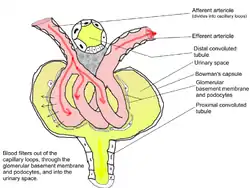

Scheme of renal tubule and its vascular supply. (1st convoluted tubule labeled at center top.) | |

The proximal tubule is the segment of the nephron in kidneys which begins from the renal pole of the Bowman's capsule to the beginning of loop of Henle. At this location, the glomerular parietal epithelial cells (PECs) lining bowman’s capsule abruptly transition to proximal tubule epithelial cells (PTECs). The proximal tubule can be further classified into the proximal convoluted tubule (PCT) and the proximal straight tubule (PST).

TEM of negatively stained proximal convoluted tubule of Rat kidney tissue at a magnification of ~55,000x and 80KV with Tight junction. Renal corpuscle

Renal corpuscle Diagram outlining movement of ions in nephron.